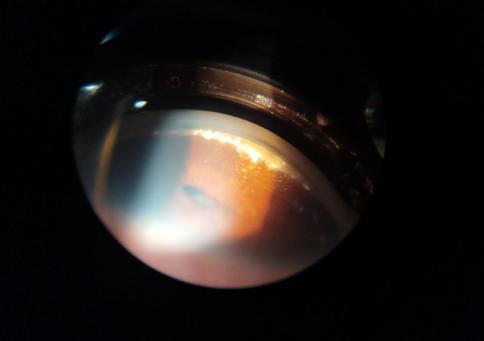

52 > Diagnóstico acertado

Colesterosis Bulbi.

Se presenta en la guardia paciente femenina de 74 años de edad con cefalea, ojo rojo y disminución de la agudeza visual (AV) en ambos ojos, con predominio de ojo derecho (OD).

BMC OD: epiescleritis, limbitis, lesión nodular con adelgazamiento escleral nasal superior, catarata nuclear 3+ córnea clara sin Tyndal.

BMC OI: córnea clara, pupila corica reactiva leve hiperemia subconjuntival con dilatación venosa inferior catarata nuclear 2+.

BMC OD: Inyección cilio-conjuntival, placa de necrosis con adelgazamiento escleral en región nasal superior, catarata total, seclusión pupilar, PQ finos y abundantes células en cámara anterior.

BMC OI: Adelgazamiento escleral nasal superior, dilatación venosa, sinequias posteriores y catarata nuclear 2+.

OD: Opacidad de cristalino y engrosamiento coroideo con desprendimiento de retina.

OI: Engrosamiento coroideo, se observa retina aplicada.